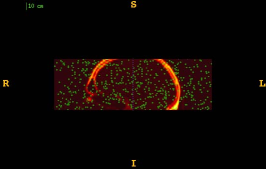

Figure 1 shows the examples of pixel selection masks generated using tested approaches at the highest resolution level for pixel sampling rate 0.5%. It is obvious that the samples generated with the URS approach are extremely spread, whereas the samples generated with the GMS approach are overly concentrated along the gradient magnitude structures present in the image. The proposed approach produces samples that balance those two extremities.